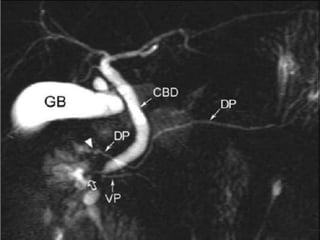

MRCP

 Dorsal pancreatic duct has a constant caliber

 Crosses the common bile duct anteriorly

 Separated from a smaller ventral duct

 Esp. If secretin stimulated MRCP is used

 Secretin acts as a hydrographic endogenous contrast

agent

MRCP  Dorsal pancreaticduct has a constant caliber  Crosses the common bile duct anteriorly  Separated from a smaller ventral duct  Esp. If secretin stimulated MRCP is used  Secretin acts as a hydrographic endogenous contrast agent